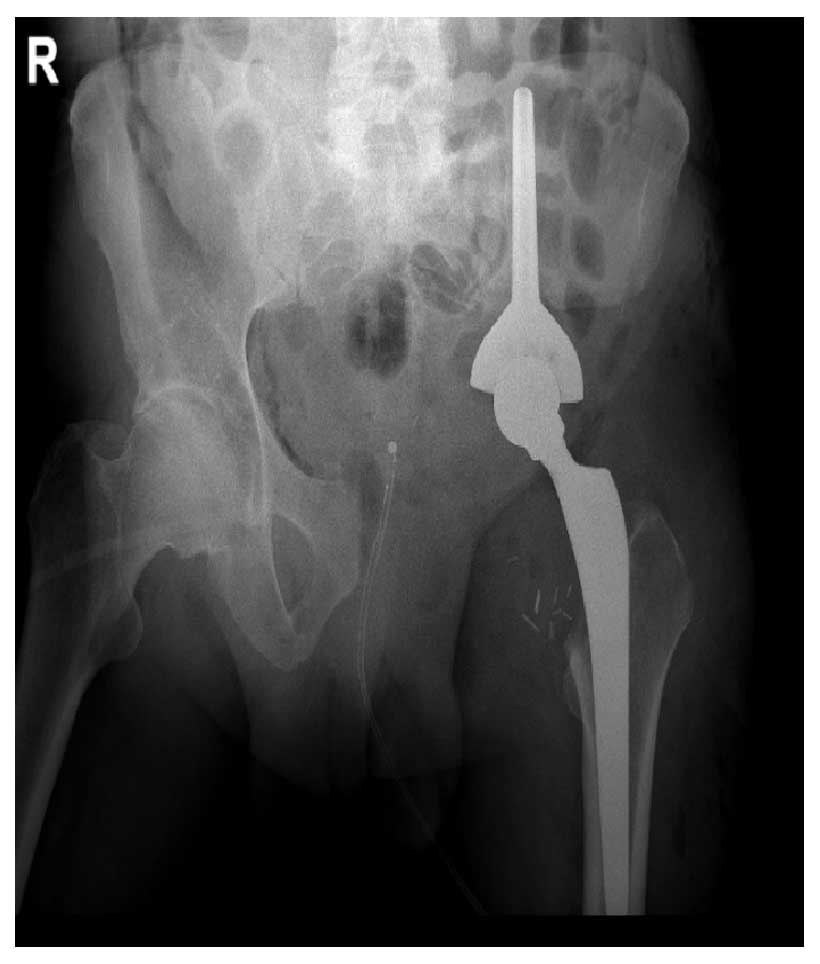

Ameliyat Sonrası: Röntgende internal hemipelvektomi sonrası Lumic protez uygulanımı görülmekte.